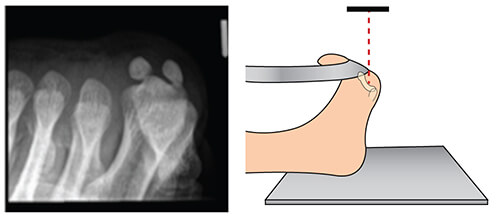

Sesamoid Bone X Ray Collection 2022 Sesamoid Bone X Ray Collection 2022

Sesamoid Bone X Ray

Sesamoid fracture | Radiology Reference Article | Radiopaedia.org Radiology Review - Sesamoid fracture | Axis Sports Med Toes (sesamoid view) | Radiology Reference Article | Radiopaedia.org Sesamoid | Radiology Reference Article | Radiopaedia.org Sesamoid bone - Wikipedia Sesamoid Bone X Ray